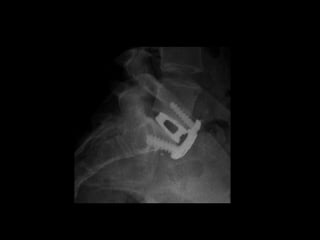

benefits Anterior interbody • anterior muscle-splitting only • minimal tissuetrauma indications • isolated degeneration • L5-S1 (L4-5) • no need to enter canal • thin, no previous major abdominal surgery FUSION FOR LOW BACK PAIN

benefits Transforaminal interbody • allows nerve decompression • allows alllevels • familiarity indications • not suitable for ALIF • nerve compression esp foraminal compression • correction of deformity